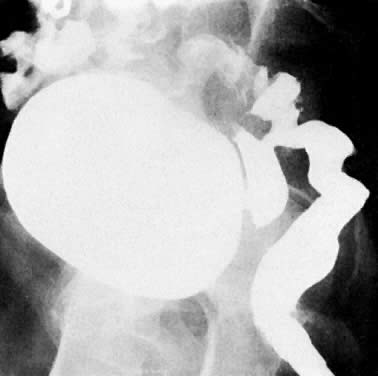

Previously, EU and retrograde pyelography have been the principal radiologic methods for examination of the urinary tract. As the tumor encases the ureter, a narrowed segment occurs (Fig. 36). The renal pelvis and calices and the ureter proximal to the involved area dilate (Fig. 37). With further involvement, the kidney ceases to function. Patients who have had a radical hysterectomy frequently have proximal ureterectasis to just below the pelvic brim. This radiologic finding lasts 6 to 12 months, and findings then gradually return to normal. The normal or narrowed distal ureters also are pulled medially secondary to the surgical procedure.

Fig. 36. Blocking ureterogram shows narrowed area in left distal ureter ( between arrows) in a patient wtih endometrial carcinoma.

Fig. 37. Excretory urogram shows dilated right collecting system to the ureterovesical junction in a patient with cervical carcinoma.